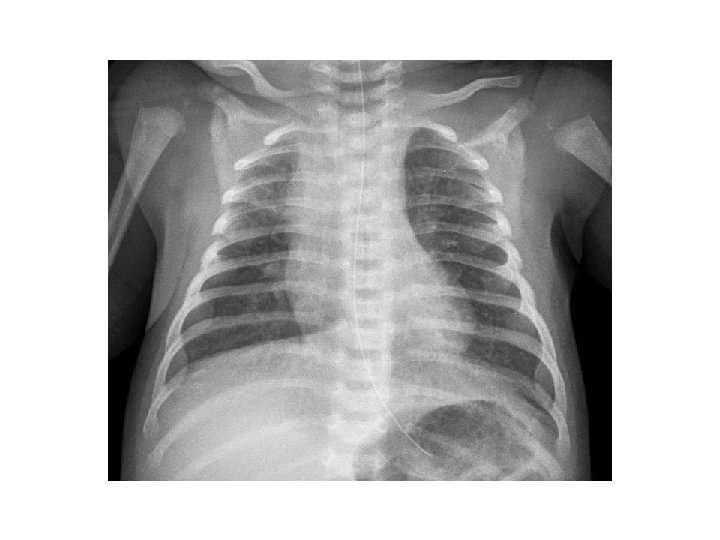

Ricovero in TIN Breve tentativo in NIPPV fallito Intubata SIMV PIP 24 cm. H 2 O PEEP 5, 5 cm. H 2 O FR 30 Ti 0, 4 10 L/min Fi. O 2 45% Sedazione: clonidina, fentanest, midazolam Terapia : Ampicillina, gentamicina, claritromicina Aerosol salina 3% + adrenalina CVC: NPT

Ricovero in TIN 02/02 Ore 12. 00 Intubata SIMV PIP 24 cm. H 2 O PEEP 5, 5 cm. H 2 O FR 60 Ti 0, 4 Fi. O 2 45% 10 L/min

Ricovero in TIN 2/02 HFOV Fi. O 2 40% 20 L/min Hz 11, 5 Ti 0, 33 ΔP 26 MAP 13, 5 Terapia : Ampicillina, gentamicina , claritromicina Aerosol salina 3% + adrenalina Teofillina Betametasone per os